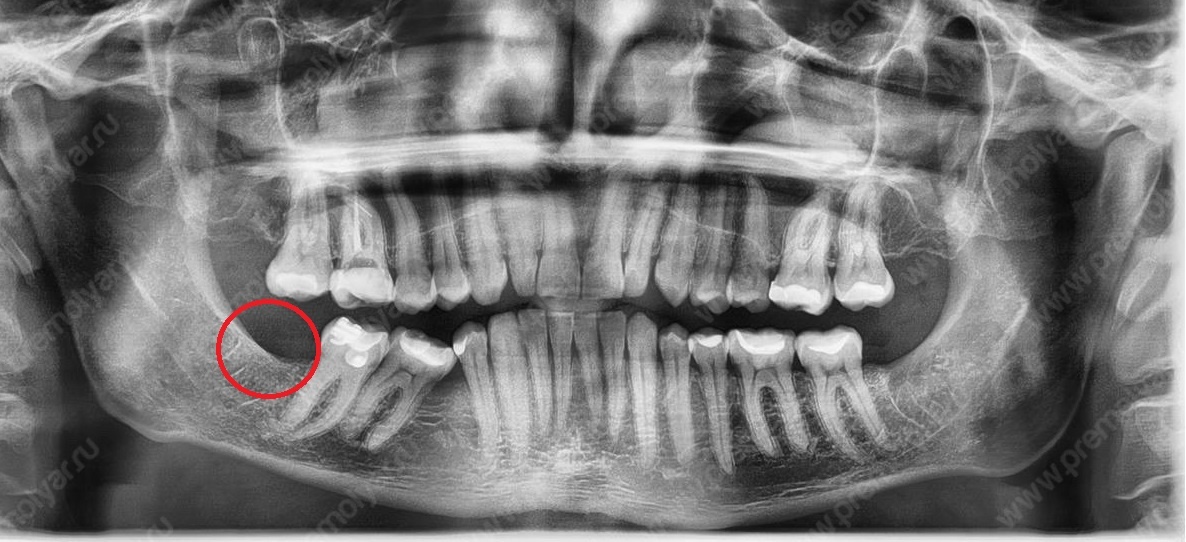

На рентгенограмме «До» мы видим отсутствие места для имплантации отсутствующего премоляра (зуба 4.5).

Прогресс через 4 месяца после установки минивинта.